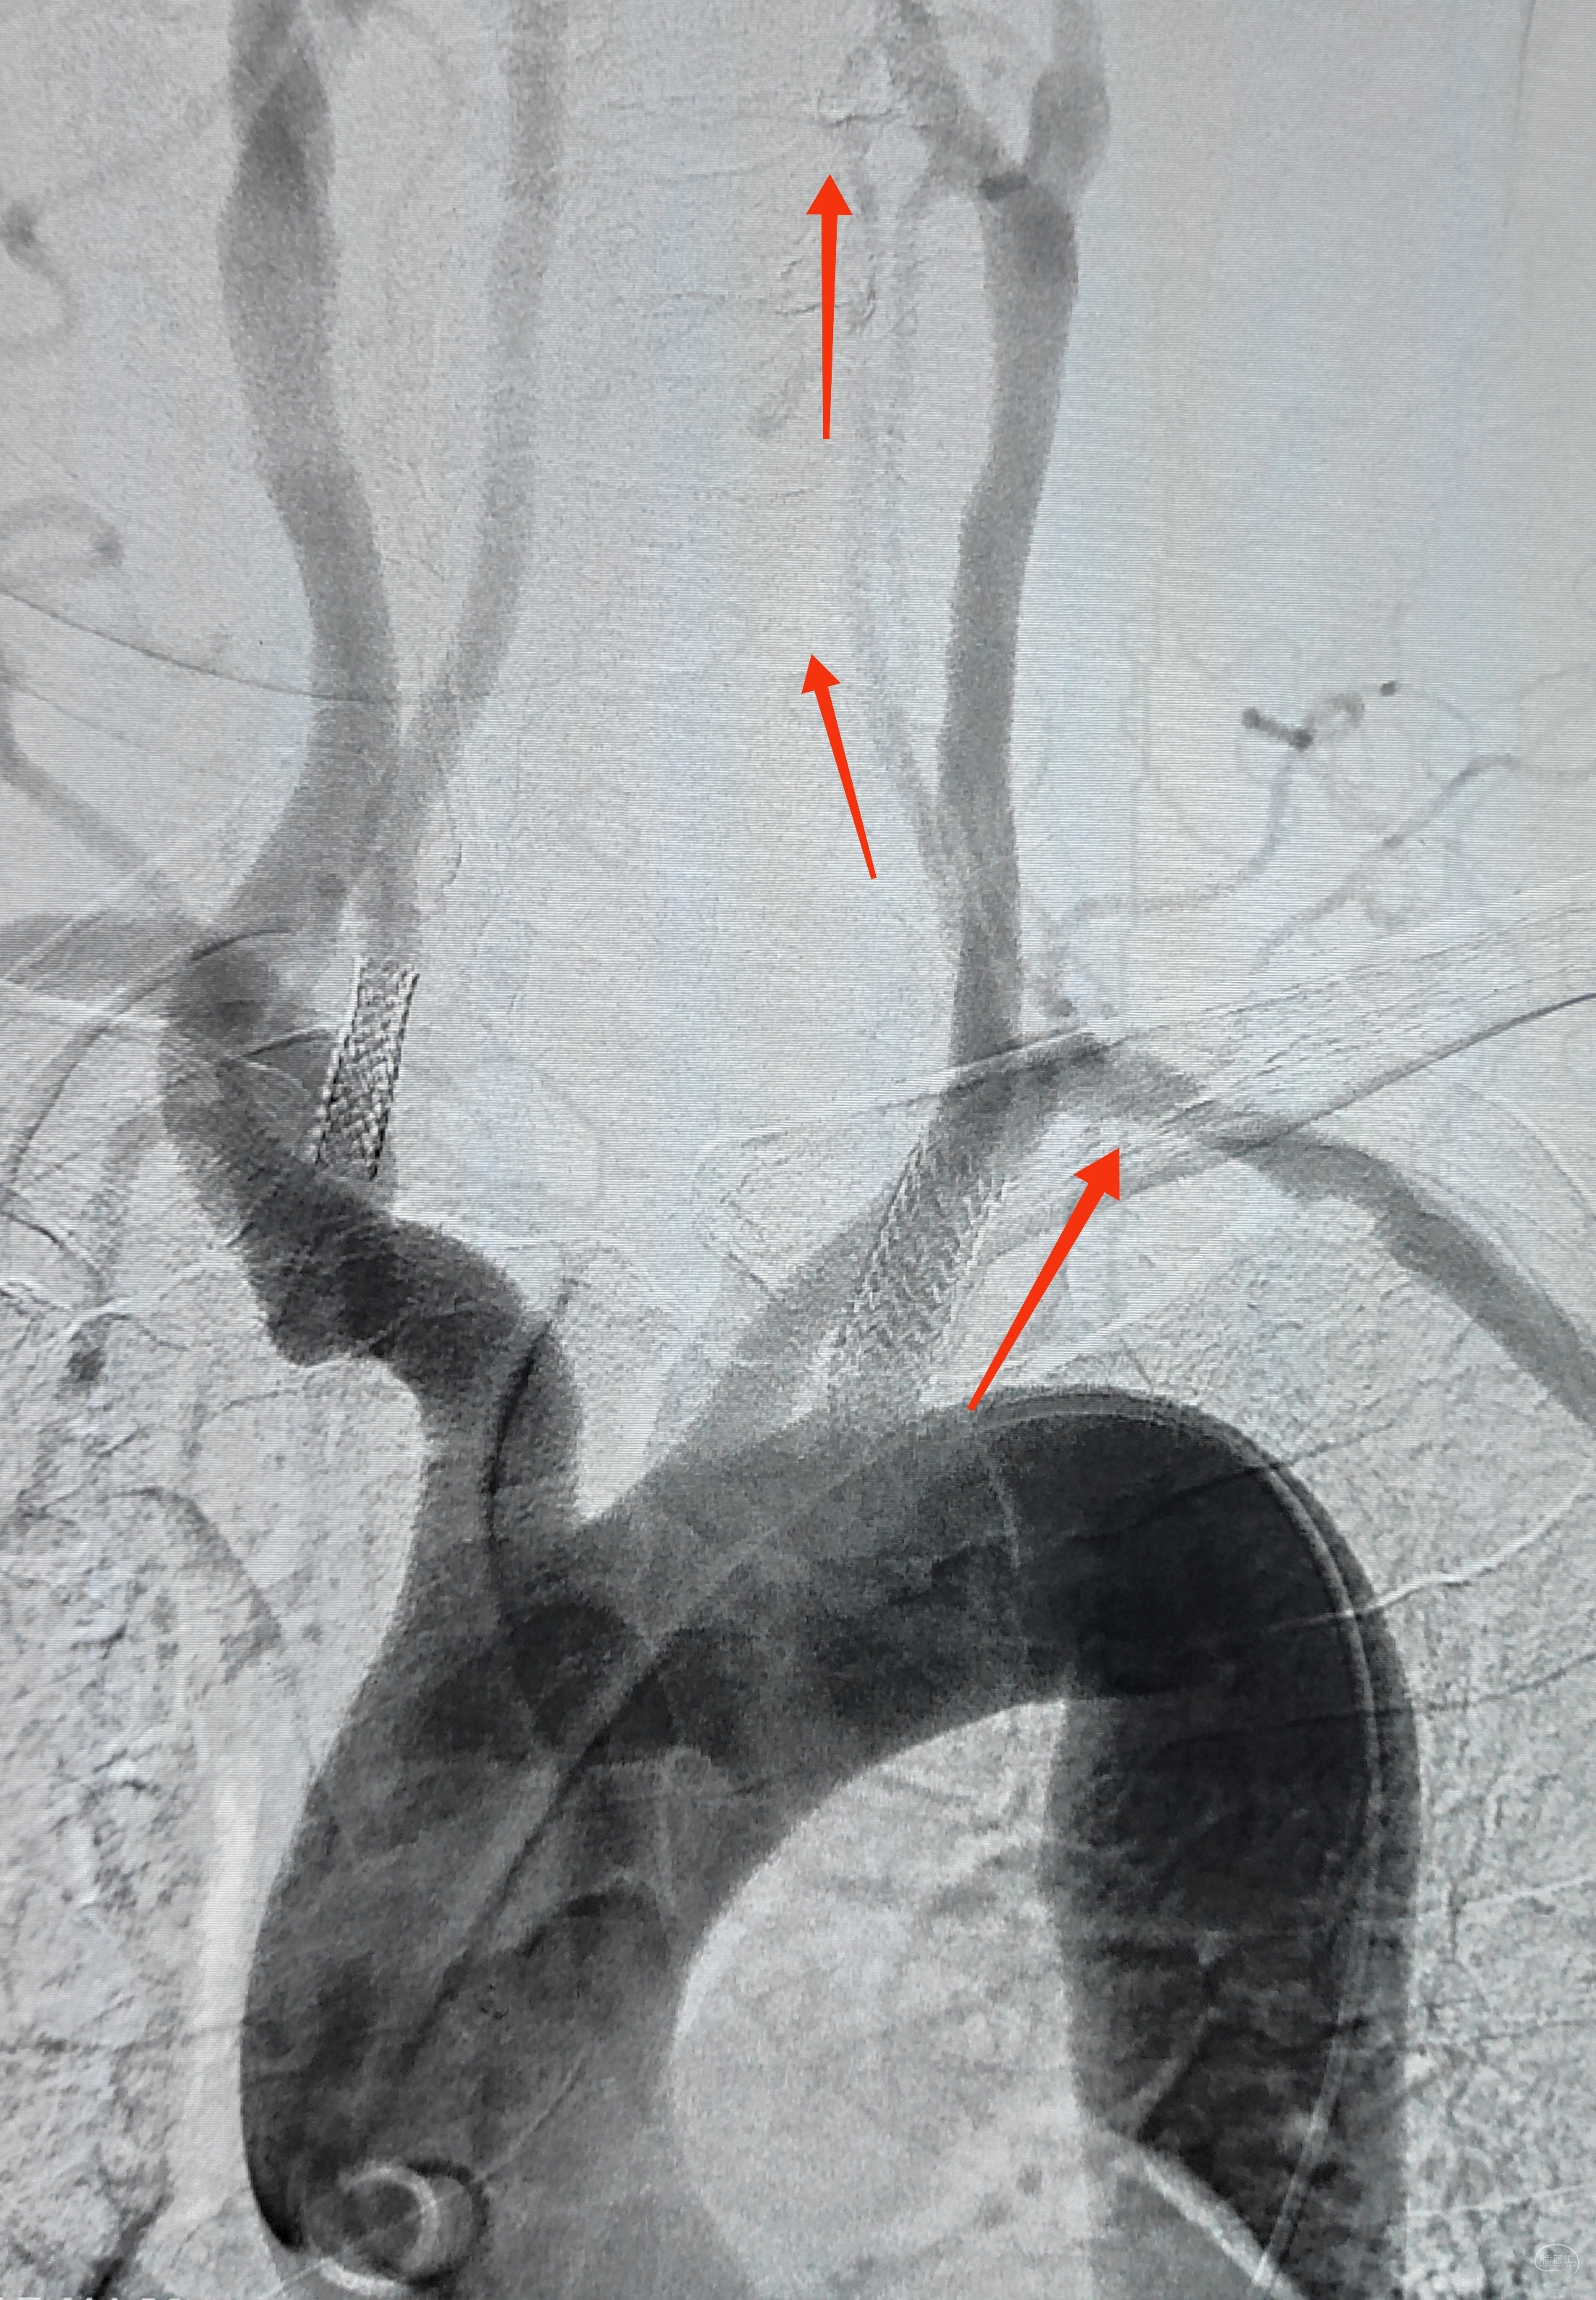

弓上造影初见:问题(一)左侧锁骨下动脉闭塞,主诉为头晕,双上肢收缩压差>20mmHg,这就是祸根?接着看弓上造影晚期像。

弓上造影晚期:剂量因素,逆流盗血隐隐可见,复合预期,那就看看对侧椎动脉情况吧